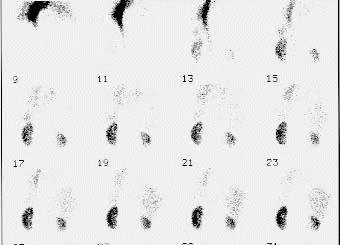

CaseTN04

- Age/Sex: 56M

- Chief Complaint: 腎移植のドナー

- Clinical Course:

- Lab. Data:

- Images:

- Tc-99m MAG3,坐位

- Blood flow

phase

- Cortical-Excretory

phase

- renogram

- DIP 10 min (左)20min

(右)立位

- X-CT:

左右の容積計測値 R/L比=0.8